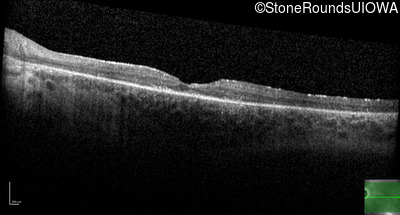

Optical Coherence Tomography - Left - 20/50

Exemplar / OCT Stack

OCT Stack